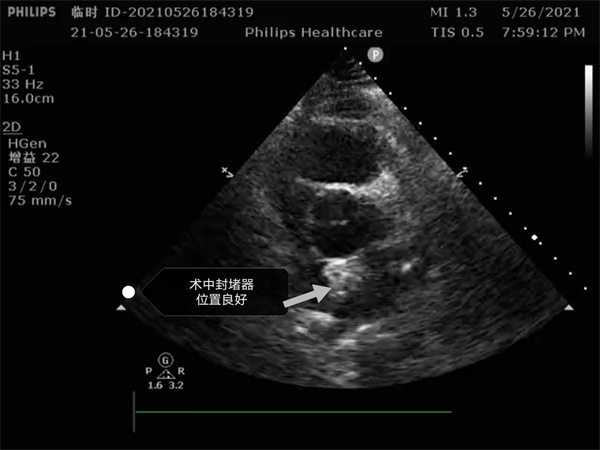

尤其是患者是個(gè)三房心,正常的人是有二個(gè)心房,這是一種少見的先天性心臟畸形, 如何在三房心把這個(gè)洞堵住,而且不影響心臟正常結(jié)構(gòu),是這個(gè)手術(shù)難點(diǎn)。沈主任組織全科進(jìn)行術(shù)前討論,5月26日下午5點(diǎn)開始手術(shù),導(dǎo)絲如何在不規(guī)則的只有米粒大小的卵圓孔里通過,鞘管如何通過,如何進(jìn)入卵圓孔連接的副房,避免封堵器夾住隔膜,這些難點(diǎn)在術(shù)中被沈主任團(tuán)隊(duì)一一化解,手術(shù)歷時(shí)二小時(shí),隨著封堵器成功釋放,導(dǎo)管室外響起來熱烈的掌聲。

就這樣三房心合并卵圓孔未閉發(fā)生過三次腦梗的患者,在安康市中心醫(yī)院心內(nèi)科導(dǎo)管室成功進(jìn)行了國內(nèi)第二例介入封堵手術(shù)。